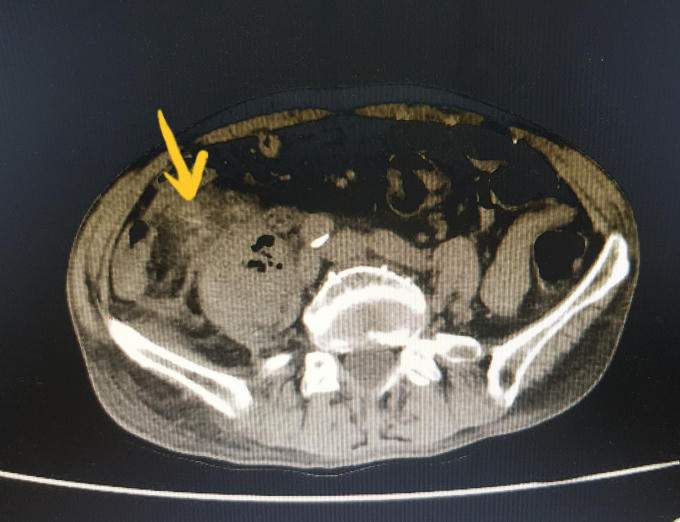

Hình ảnh chụp cắt lớp ổ bụng cho thấy, chiếc tăm xỉa rang dài 5 cm đã đâm thủng ruột cụ ông.

Sau khi thăm khám và chụp cắt lớp ổ bụng bệnh nhân, các bác sĩ phát hiện hình ảnh nghi dị vật (tăm) dài khoảng 5 cm xuyên thủng ruột vị trí hồi manh tràng, đâm vào cơ thắt lưng chậu phải gây áp xe và phản ứng viêm vùng hố chậu phải.